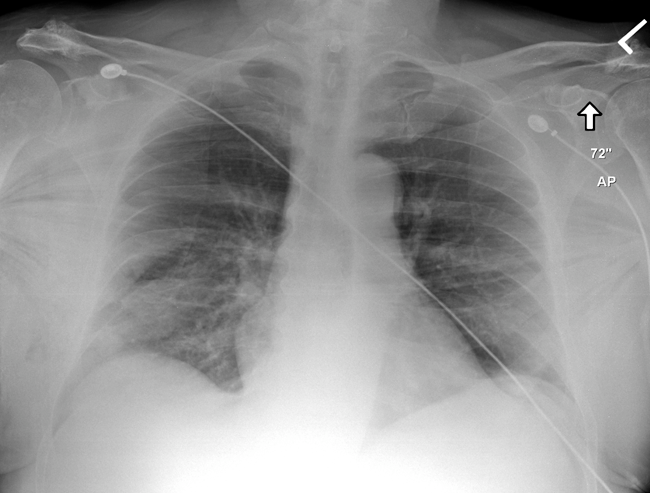

Subcutaneous Emphysema

Notice muscle fibers of pectoralis major muscles indicating air outside of the pleura

-

This finding is highly suggestive of pneumothorax (although not obviously seen on this plain film)

Follow-up CT was obtained

Pneumothorax noted to right lung along with significant subcutaneous emphysema

Also note fracture of rib on the right